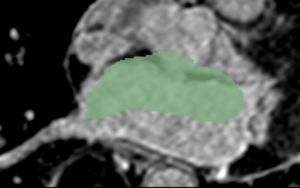

Example 2

CARMA N25 LGE.png

CARMA N25 Endo.png

Cropped MRI image overlaid with the algorithm-defined blood pool. Expert manual segmentations (white) overlaid with the algorithm-defined blood pool (green).

Note: The last segmentation (red) was derived from an image in the atlas; the other segmentations (green) were derived from similarly-cropped images, not in the atlas.